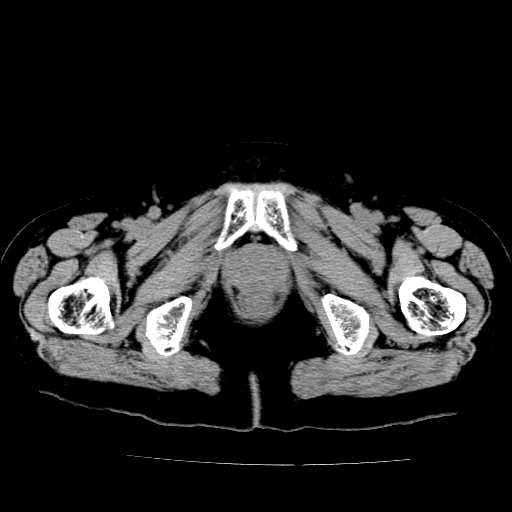

女,73岁,阴道流血一周。

宫颈不规则增大;结合临床考虑宫颈癌。建议作mri检查

1\\老年妇女突发阴道流血,常见病考虑宫颈癌.本病例宫颈部显示形态不规则,密度欠均匀,支持考虑宫 颈癌,建议mri 或阴道超声坚持

2\\但是盆腔两侧尚未见到明显肿大淋巴结等转移征象

宫颈不规则增大,左后方可见结节状突起.支持宫颈癌.

宫颈壁明显增厚,左侧为甚,宫颈癌待排,建议宫颈涂片细胞学检查。

宫颈不规则增大,周围脂肪间隙毛糙,结合临床考虑宫颈癌,盆腔内未见肿大淋巴结。